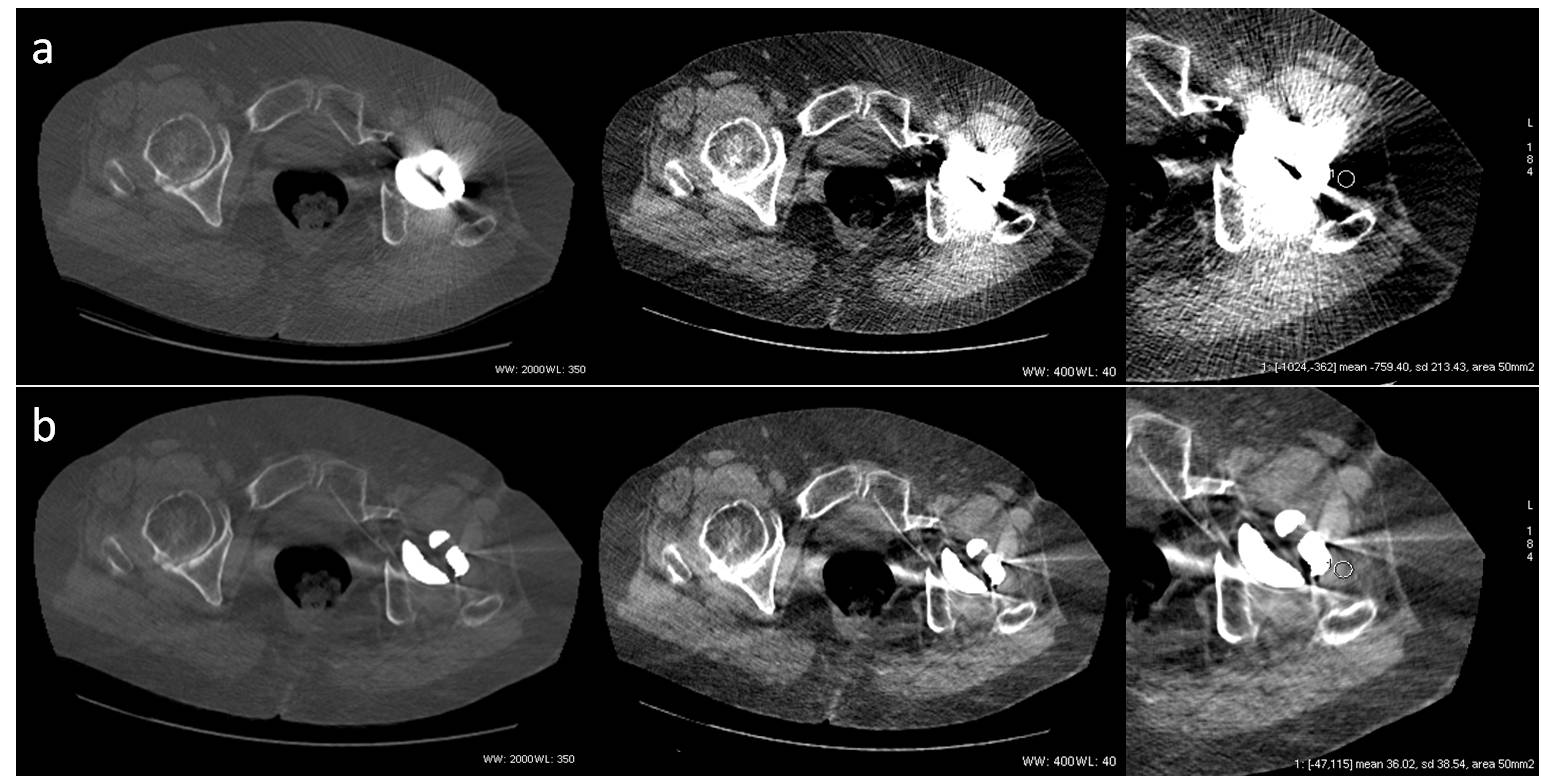

9. Morsbach F, Bickelhaupt S, Wanner GA, Krauss A, Schmidt B, Alkadhi H. Reduction of metal artifacts from hip prostheses on ct images of the pelvis: Value of iterative reconstructions. Radiology. 2013;268:237-244

11. Han SC, Chung YE, Lee YH, Park KK, Kim MJ, Kim KW. Metal artifact reduction software used with abdominopelvic dual-energy ct of patients with metal hip prostheses: Assessment of image quality and clinical feasibility. AJR. American journal of roentgenology. 2014;203:788.

15. Lewis M, Reid K, Toms AP. Reducing the effects of metal artefact using high kev monoenergetic reconstruction of dual energy ct (dect) in hip replacements. Skeletal radiology. 2013;42:275-282